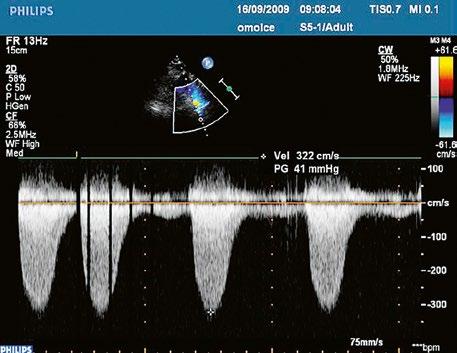

Malé restriktivní defekty komorového septa (Rogerova choroba) nevedou ke vzniku plicní hypertenze ani k srdečnímu selhání. Mají typickou vysokorychlostní dopplerovskou křivku (Obr. 45.35), odpovídající vysokém gradientu mezi levou a pravou komorou v systole a poslechovému nálezu hlučného systolického šelestu.

Obr. 45.35 CW záznam vysokorychlostního dopple rovského toku z levé do pravé komory malým restriktivním defektem komorového septa. Vysoký gradient na komorovém defektu vylučuje vysoký tlak v pravé komoře při plicní hypertenzi nebo při těžké stenóze plicnice.